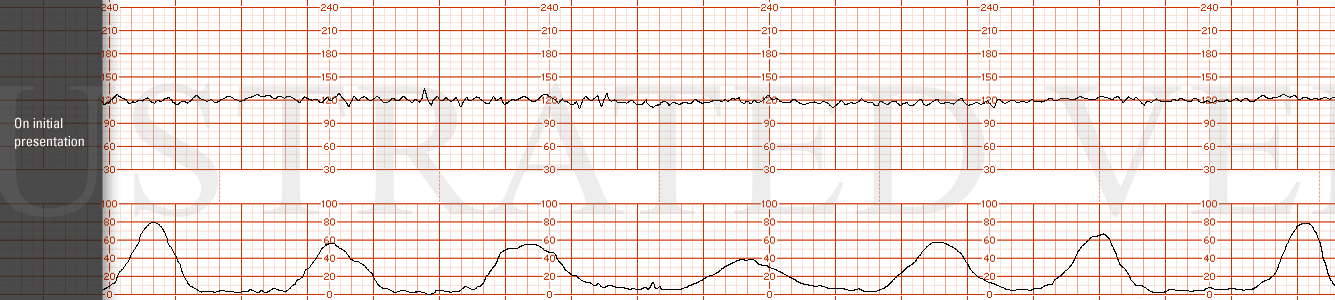

STRIP 69

1. Panel 20 minutes

Nine contractions, each 50-60 sec long, in last 20 minutes. 2nd, 3rd and 4th contraction to long, about 10 secs, 6th needs 15 secs off,

Baseline rate at +/- 150 bpm over 20 minute panel with minimal variability

Three mild-moderate variable decelerations - (varying in duration from20-35 sec each to nadir varying between 105 to 120 bpm ( 4, 10 (needs to be moved over 1 min) and 16 (move 30 secs over to right) minutes in the 20 minute segment). There is no progression in depth or duration of the decelerations - random

There is one 18-bpm acceleration at minute 8-9 in the last 20 minutes

Category 2 with mild to moderate variable decelerations and minimal variability.